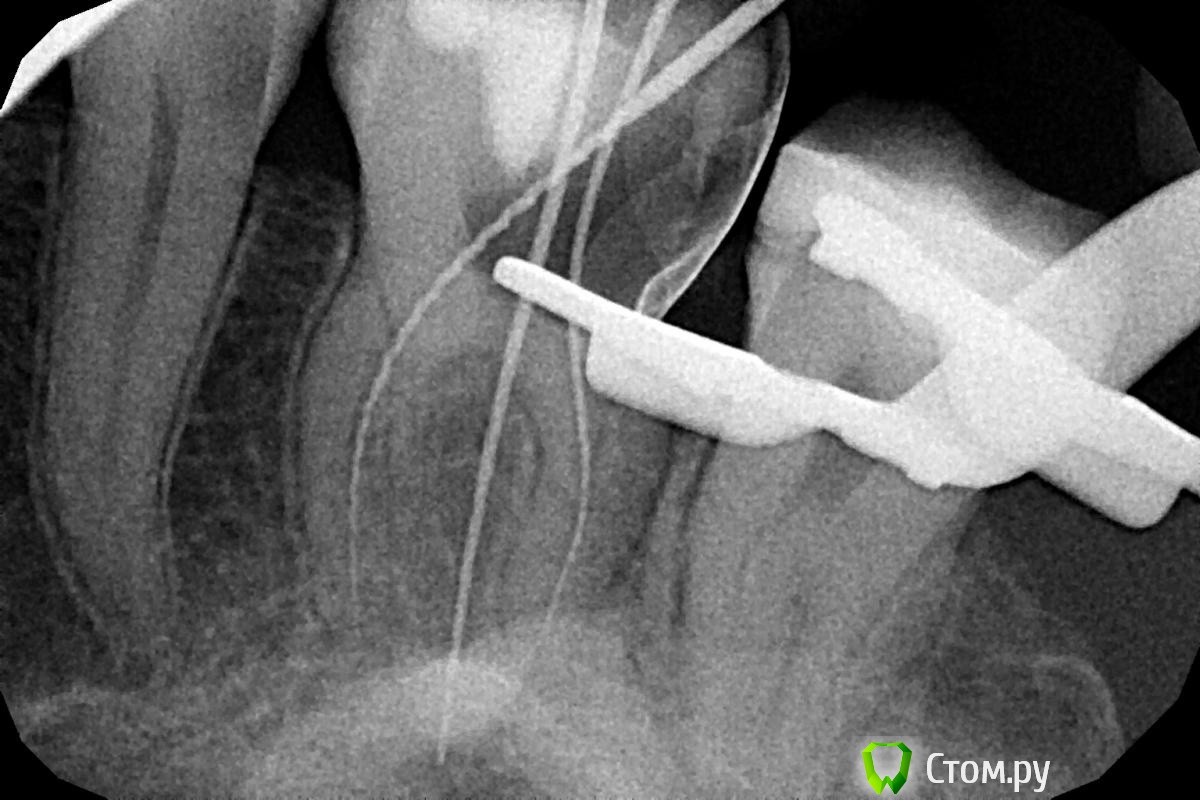

вдгиф Опубликовано 12 января, 2014 Поделиться Опубликовано 12 января, 2014 (изменено) Добрый день, прошу помощи у врачей.Посоветуйте что делать- пытаться ли извлечь инструмент и каковы прогнозы без этой рисковой процедуры. Болел зуб- на приеме у врачас-стоматолога(длился 2 часа) депульпировали зуб.СО СЛОВ ВРАЧА: "Инструмент(профайл 40-06) был сломан на финальной стадии обработки корневых каналов. Обломок инструмента зафиксирован в апикальной трети части корневого канала, поэтому недоступен для обзора в микроскоп. Извлечь его с помощью иглы от шприца(системы) http://rosmicro.ru/?p=2111 невозможно. в настоящий момент в корневых каналах 16 зуба находится гидроокись кальция, замешанная на дистиллированной воде. Зуб закрыт временной пломбой."2 дня была температура(возможно орз- не факт что от зуба). Зубвроде не болит, но дискомфорт какой то есть при жевании.Смущает инфекция возле корня и возможность обойти обломок. Всем откликнувшимся- заранее спасибо! Изменено 12 января, 2014 пользователем вдгиф Ссылка на комментарий

Stomart Опубликовано 12 января, 2014 Поделиться Опубликовано 12 января, 2014 Если был пульпит, то инфекции возле корня нет. Если нет возможности извлечь инструмент, то обойти и запломбировать (на втором снимке он вроде как обойден). А еще поискать четвертый канал. 2 Ссылка на комментарий

Kolchanov Опубликовано 12 января, 2014 Поделиться Опубликовано 12 января, 2014 Судя по описанию и снимку, лечение проводилось как надо. К сожалению, инструменты иногда ломаются. Но, учитывая то, что зуб был витальный (пульпит), инструмент сломан в конце обработки, была изоляция зуба от полости рта, то можно рассчитывать на высокий успех лечения даже если инструмент не будет извлечен. Запломбируйте каналы у того же доктора и восстановите его рекомендованным способом (коронка, скорее всего). Все будет в порядке. Ссылка на комментарий

Scrabble Опубликовано 15 января, 2014 Поделиться Опубликовано 15 января, 2014 Выступлю в защиту доктора: коффердам использовался, микроскоп есть, насколько мне видно, док даже дистальную стенку восстановил перед эндо(это несомненный плюс) А инструменты не ломаются только у тех, кто в каналах не работает. Если ломаются-поверьте, мы(то есть, стоматологи) расстраиваемся зачастую больше, чем пациенты. Четвёртого канала в Вашем случае может и не быть(хотя мне кажется, что поискать стоит) Ссылка на комментарий